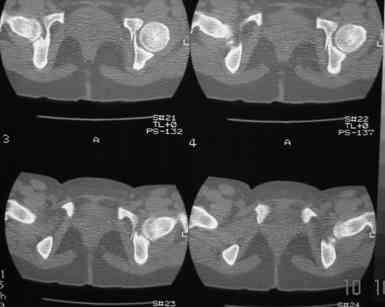

В больнице вправили вывих бедра, три недели на вытяжении. Беспокоят боли в левом тазобедренном суставе и левом крестцово-подвздошном сочленении. Ходит с тростью. Снимок - в приложении. Направил на КТ, заключение: разрыв симфиза и левого крестцово-подвздошного сочленения, переломы крыши и заднего края вертлужной впадины, горизонтальной ветви лонной кости слева.

Уважаемый д-р Булахтин, на мой взгляд единственное повреждение требующее синтеза - застарелый разрыв лона. Низкий перелом передней колонны безопасен, повреждения свода не вижу, неясно что было сзади (скорее боковая масса)лучше сделать обзорный снимок прямой и Inlet.

Очень похоже на повреждение от бокового сжатия.

Признаков разрыва сочленения не вижу, м.б. контрлатеральный перелом боковой массы.

Если был задний вывих, то повреждение должно локализоваться сзади. В данном случае перелом спереди, как результат сдавления лонного сочленения.

Т.е. головка не работала молотком.

Синтез лонного сочленения восстановит стабильность тазового кольца.